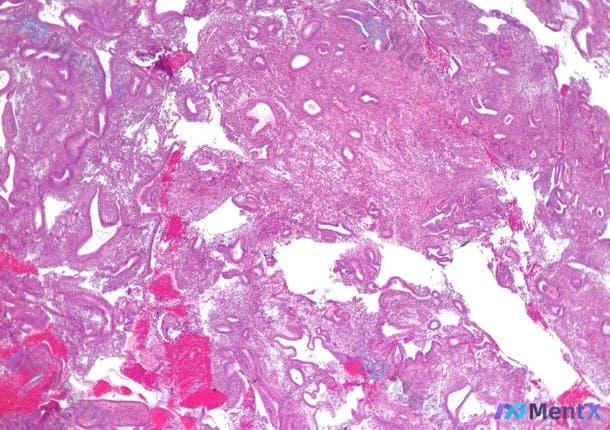

- 内膜活检(H&E影像分析):

- 腺体管状为主,排列尚规则,无明显拥挤/背靠背/复杂结构;

- 腺上皮高柱状,核极性好,无明显异型,可见生理性有丝分裂;

- 间质致密,无分泌期改变(无腺体锯齿状扩张、基底侧空泡);

- 可见红细胞渗出,无明显炎症细胞浸润;

- 结论倾向:增殖期子宫内膜,无典型增生或恶性证据。